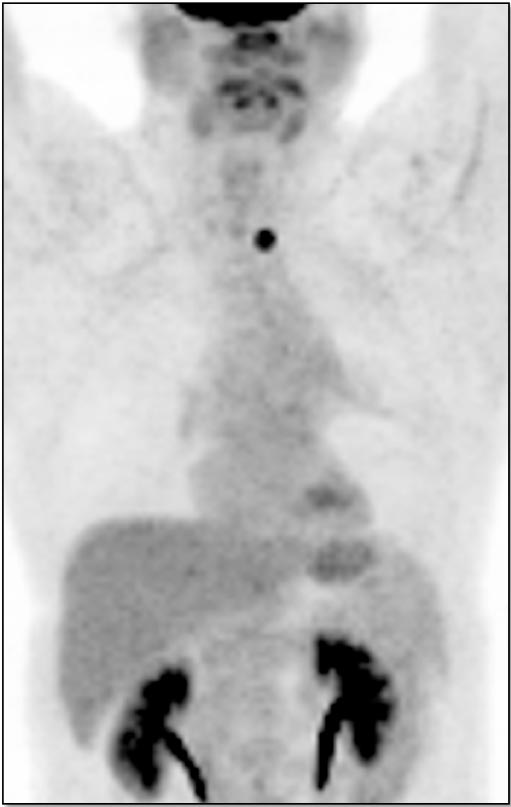

- Maximum Intensity Projection (MIP)

3. Excellent Views: The MIP, Coronal & Sagittal Images

- 3-D Rotating MIP & Coronal “Quick MIP”